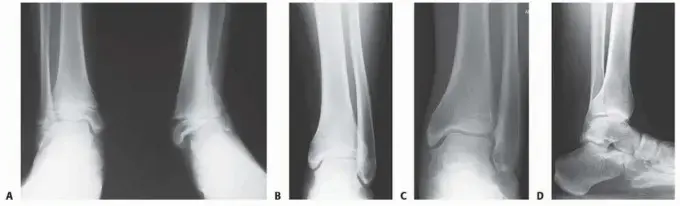

2. الأشعة السينية (X-ray):

• تُعد الأشعة السينية هي الفحص الأساسي لتحديد التشوهات العظمية. يتم التقاط صور متعددة للكاحل والقدم والساق بالكامل في أوضاع مختلفة (تحميل الوزن، بدون تحميل).

• باستخدام مقاييس وزوايا محددة، يستطيع الدكتور هطيف قياس درجة الانحراف الزاوي أو التوائي وتحديد الموقع الدقيق للتشوه في عظم الساق السفلي. هذه القياسات حاسمة للتخطيط الجراحي.